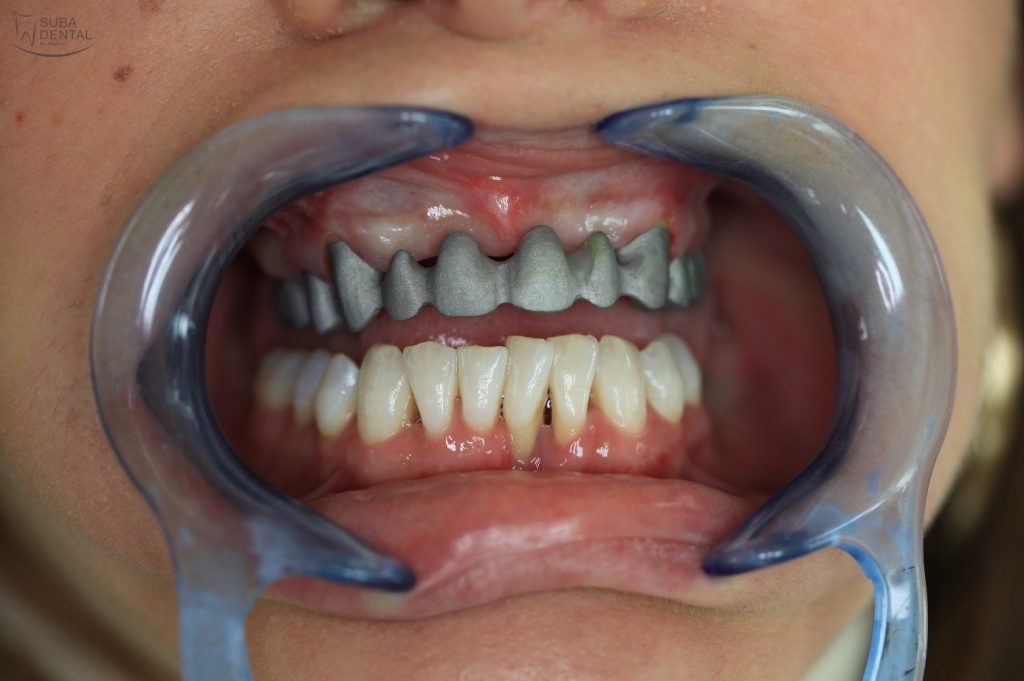

Mivel páciensünk mindig is szeretett volna egy kicsit fehérebb fogakat, így a professzionális fogkő-eltávolítás után Zoom 2 rendelői LED lámpás fogfehérítést végeztünk,

hogy az új fogszínhez ki tudjuk választani a koronák színét a tökéletes és fehér mosoly elérése érdekében.